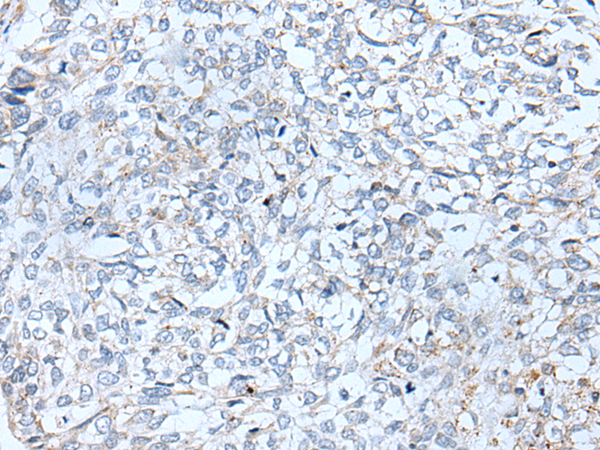

分类: 科研抗体货号: P05898别名: MKS12应用: WB,IHC反应种属: Human